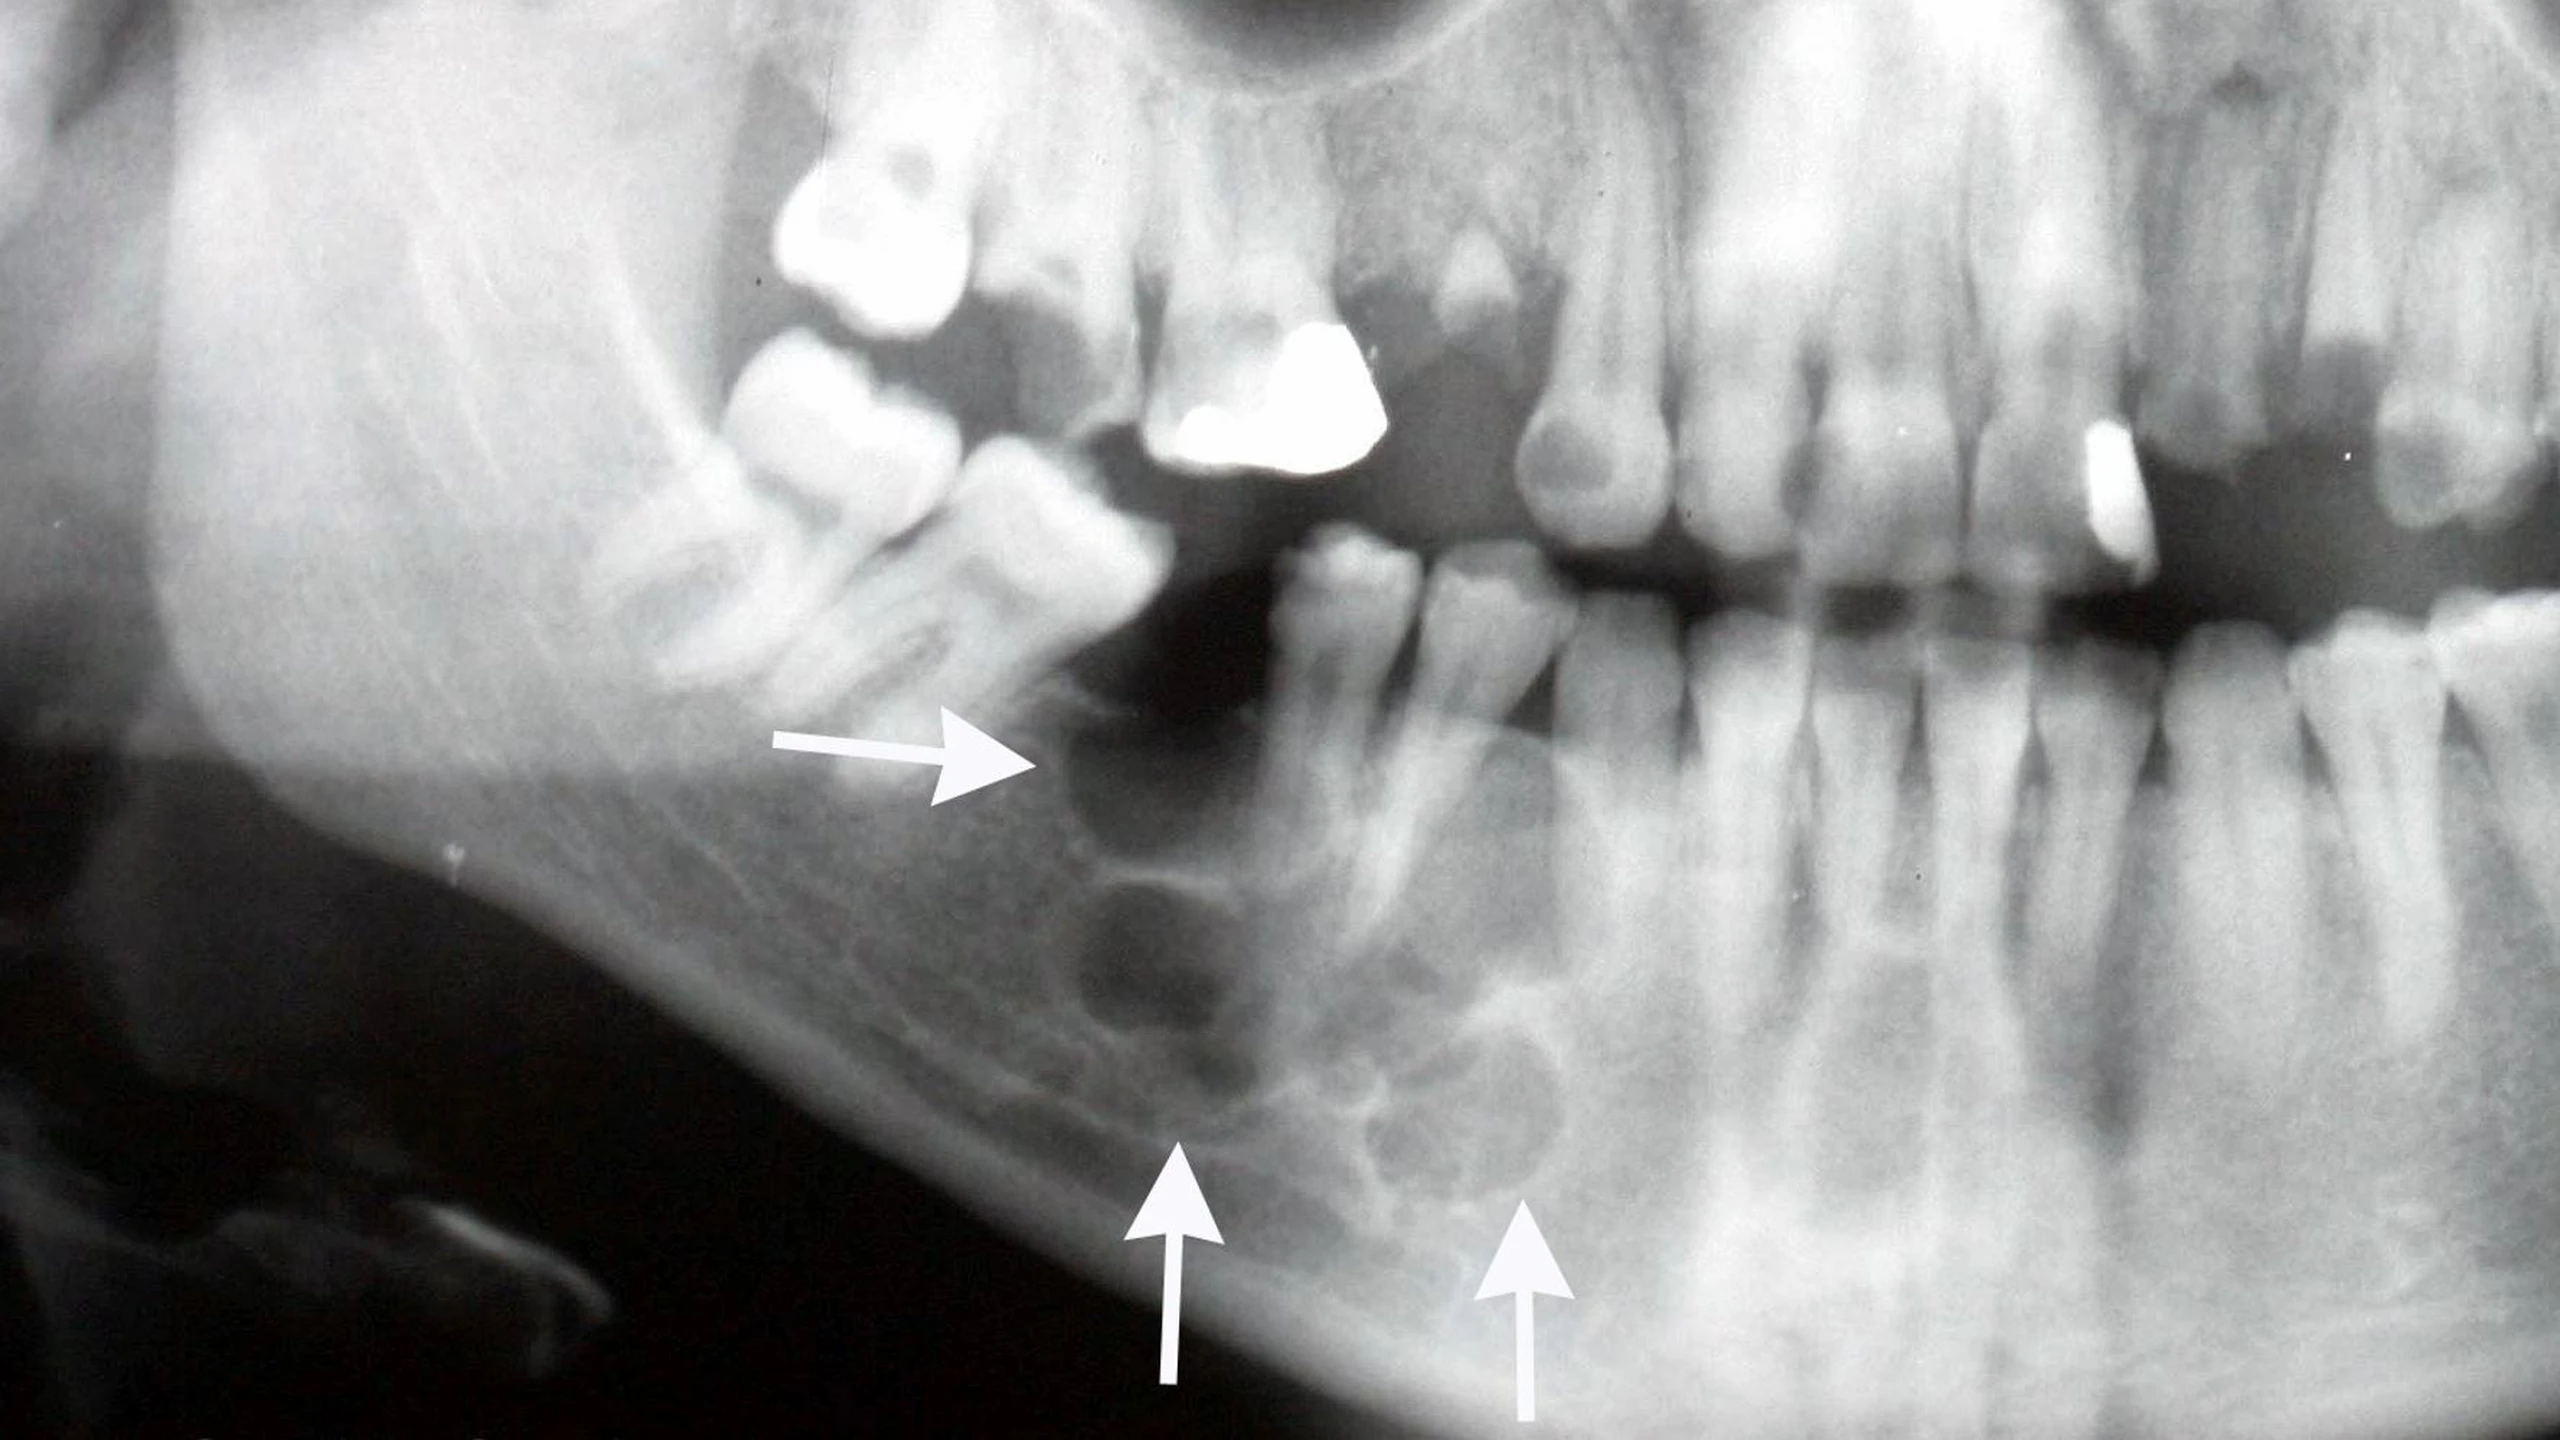

U men xương hàm là một khối u hiếm gặp và phát triển chậm trong hàm của bạn, ở khoảng trống phía sau răng hoặc hàm. U men xương hàm đa phần là lành tính tuy nhiên vẫn có thể tiến triển thành ác tính. Bệnh thường được phát hiện tình cờ khi bạn khám nha khoa hoặc đến khi đã gây tình trạng biến dạng mặt. Nếu không được điều trị, u men xương hàm có thể làm hỏng xương hàm và các bộ phận khác trong miệng. Phẫu thuật là phương pháp điều trị hiệu quả nhất để chữa khỏi u men xương hàm, giúp ngăn ngừa những tổn thương nghiêm trọng hơn. Do khả năng tái phát cao sau điều trị, việc theo dõi định kỳ sau phẫu thuật là rất cần thiết.

U men xương hàm là khối u có nguồn gốc từ tế bào tạo men. Đa số các trường hợp là u lành tính tuy nhiên có thể tiến triển thành dạng ác tính như u men xương hàm ác tính hoặc ung thư biểu mô nguyên bào tạo men.

U men xương hàm có thể lây lan cục bộ và xâm lấn các mô xung quanh ở hàm và khoang miệng. Chúng có thể lây lan đến xương và có thể xâm lấn các mô mềm nếu có đủ thời gian. Tuy nhiên vì u men xương hàm thường là khối u lành tính nên khả năng di căn hạch, đến các cơ quan ở xa hiếm khi xảy ra. Ước tính u men xương hàm ác tính chỉ chiếm chưa đến 1% tổng các trường hợp được chẩn đoán u men xương hàm.

U men xương hàm phổ biến ở hàm dưới hơn so với hàm trên và hàm trước. U men xương hàm thường xuất hiện ở vùng răng cối lớn thứ ba (răng khôn), nơi tế bào tạo men còn tồn tại. Các khối u này thường phát triển chậm, có tính chất phá hủy do đó có thể dẫn đến bệnh lý khác nghiêm trọng và cần điều trị bằng phẫu thuật.

U men xương hàm có thể được phát hiện sớm mà chưa biểu hiện triệu chứng gì khi bạn đi khám răng định kỳ. Khi bệnh có biểu hiện bất kỳ triệu chứng nào hãy đến gặp bác sĩ nha khoa ngay.